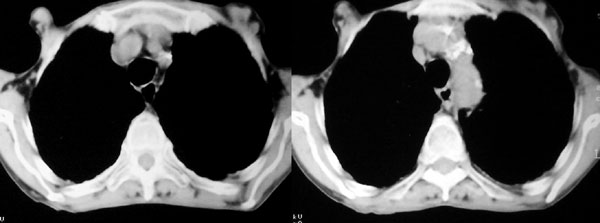

f 76 间断咳嗽 咳痰1年余 发热不明显 身体削瘦

2、纵隔气管前、隆突下、内乳组、心右前间隙以及右侧腋窝内均可见肿大的淋巴结节;

诊断意见:

1、右侧中央型(空洞性)肺癌并双肺受累(包括转移、阻塞性炎症、癌性淋巴管炎);纵隔、右侧腋窝内淋巴结肿大、转移;右侧胸膜增厚粘连,胸腔少量积液;

2、双上肺陈旧性结核。

3、慢性支气管炎、肺气肿。